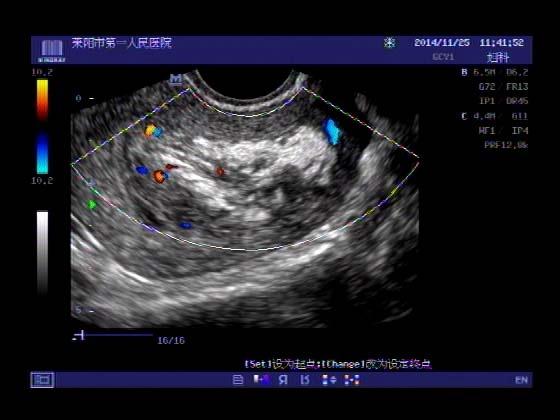

超声入门贴379---------粘膜下肌瘤(阴超的魅力)

女,43岁,月经量多3个多月,加重一个月

外院彩超检查提示:子宫后肌壁略高回声团------肌瘤?息肉?,盆腔少量积液

今天来我院检查:

巧妇难为无米之炊,经腹部超声确实很难定,阴超一目了然,乡镇医院诊断水平的提高更迫切的需要高档仪器的引进!